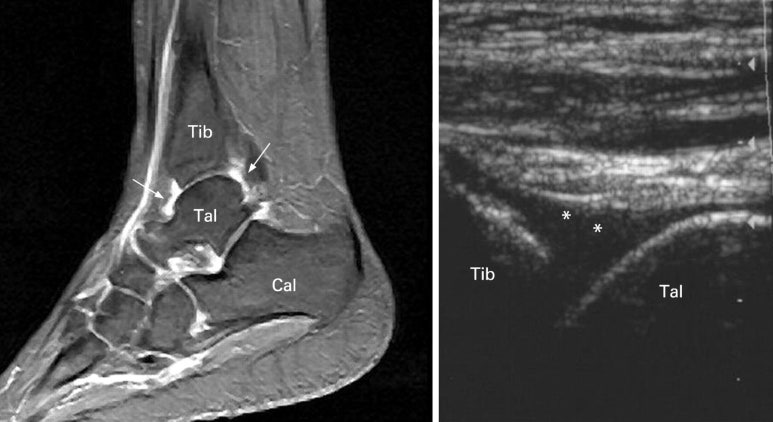

좌측: 정상 발목 인대, 우측: 염좌로 손상되어 퉁퉁 부은 발목 인대 / 이미지 출처: 근골격계 초음파, S Bianchi, 길호영 역, E Public, 2009.

발목 염좌시 충격으로 발생한 관절낭 부종

위 그림처럼 주변 관절도 손상되어 물이 차 있는 경우도 많습니다.

발목 인대 손상 후 동반되는 비골근 건초염 / 이미지 출처: 근골격계 초음파, S Bianchi, 길호영 역, E Public, 2009.